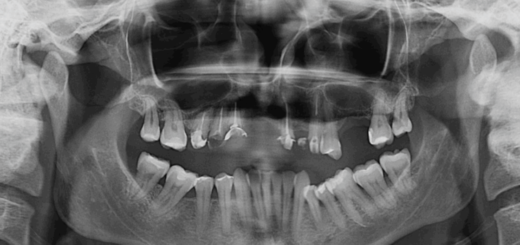

La endodoncia, también conocida como tratamiento de conducto, es un procedimiento que involucra la eliminación cuidadosa de la pulpa dental infectada o inflamada, la limpieza y desinfección del conducto radicular y su posterior sellado para prevenir futuras infecciones. Este tratamiento permite salvar el diente natural y evitar la extracción.

Caries profunda: Cuando una caries dental alcanza la pulpa dental, puede causar una infección y provocar dolor intenso. La endodoncia es necesaria para eliminar la infección y aliviar el dolor.

Traumatismo dental: Un golpe o lesión en el diente puede dañar la pulpa dental, lo que puede requerir endodoncia para salvar el diente.

Infección dental: Si una infección bacteriana se propaga desde las encías hasta la pulpa dental, puede ser necesario realizar una endodoncia para eliminar la infección y salvar el diente.